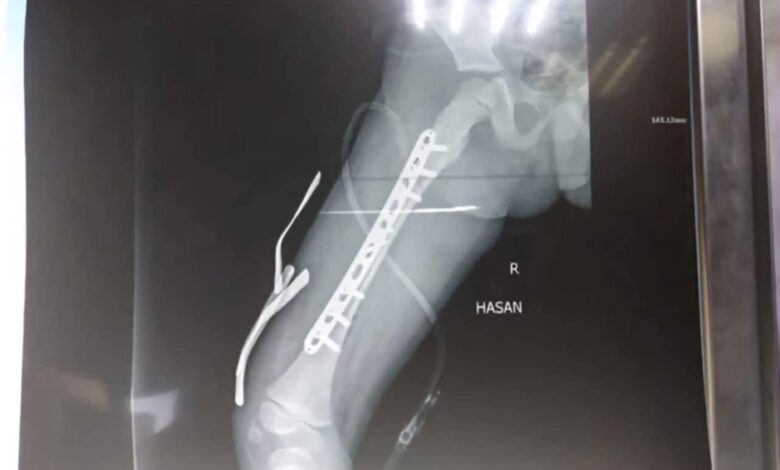

اجرى فريق طبي مختص بجراحة العظام والكسور في مستشفى الحلة التعليمي عملية جراحية وصفت فوق الكبرى لطفل يبلغ من العمر 6 أعوام يعاني من كسر في عظم الفخذ ناتج عن سقوطه من مرتفع .

اخصائي جراحة العظام والكسور الدكتور اشرف الحسيني بين ان المريض يعاني من تشوه الفخذ الأيمن نتيجة الكسر حيث اجريت له عملية تثبيت كسر عظم الفخذ الايمن عبر استخدام الصفيحة المغلقة مع البراغي ، مؤكداً نجاح العملية واستقرار الحالة الصحية للمريض بجهود الكادر الطبي والتمريضي والصحي والتخدير في صالة العمليات .